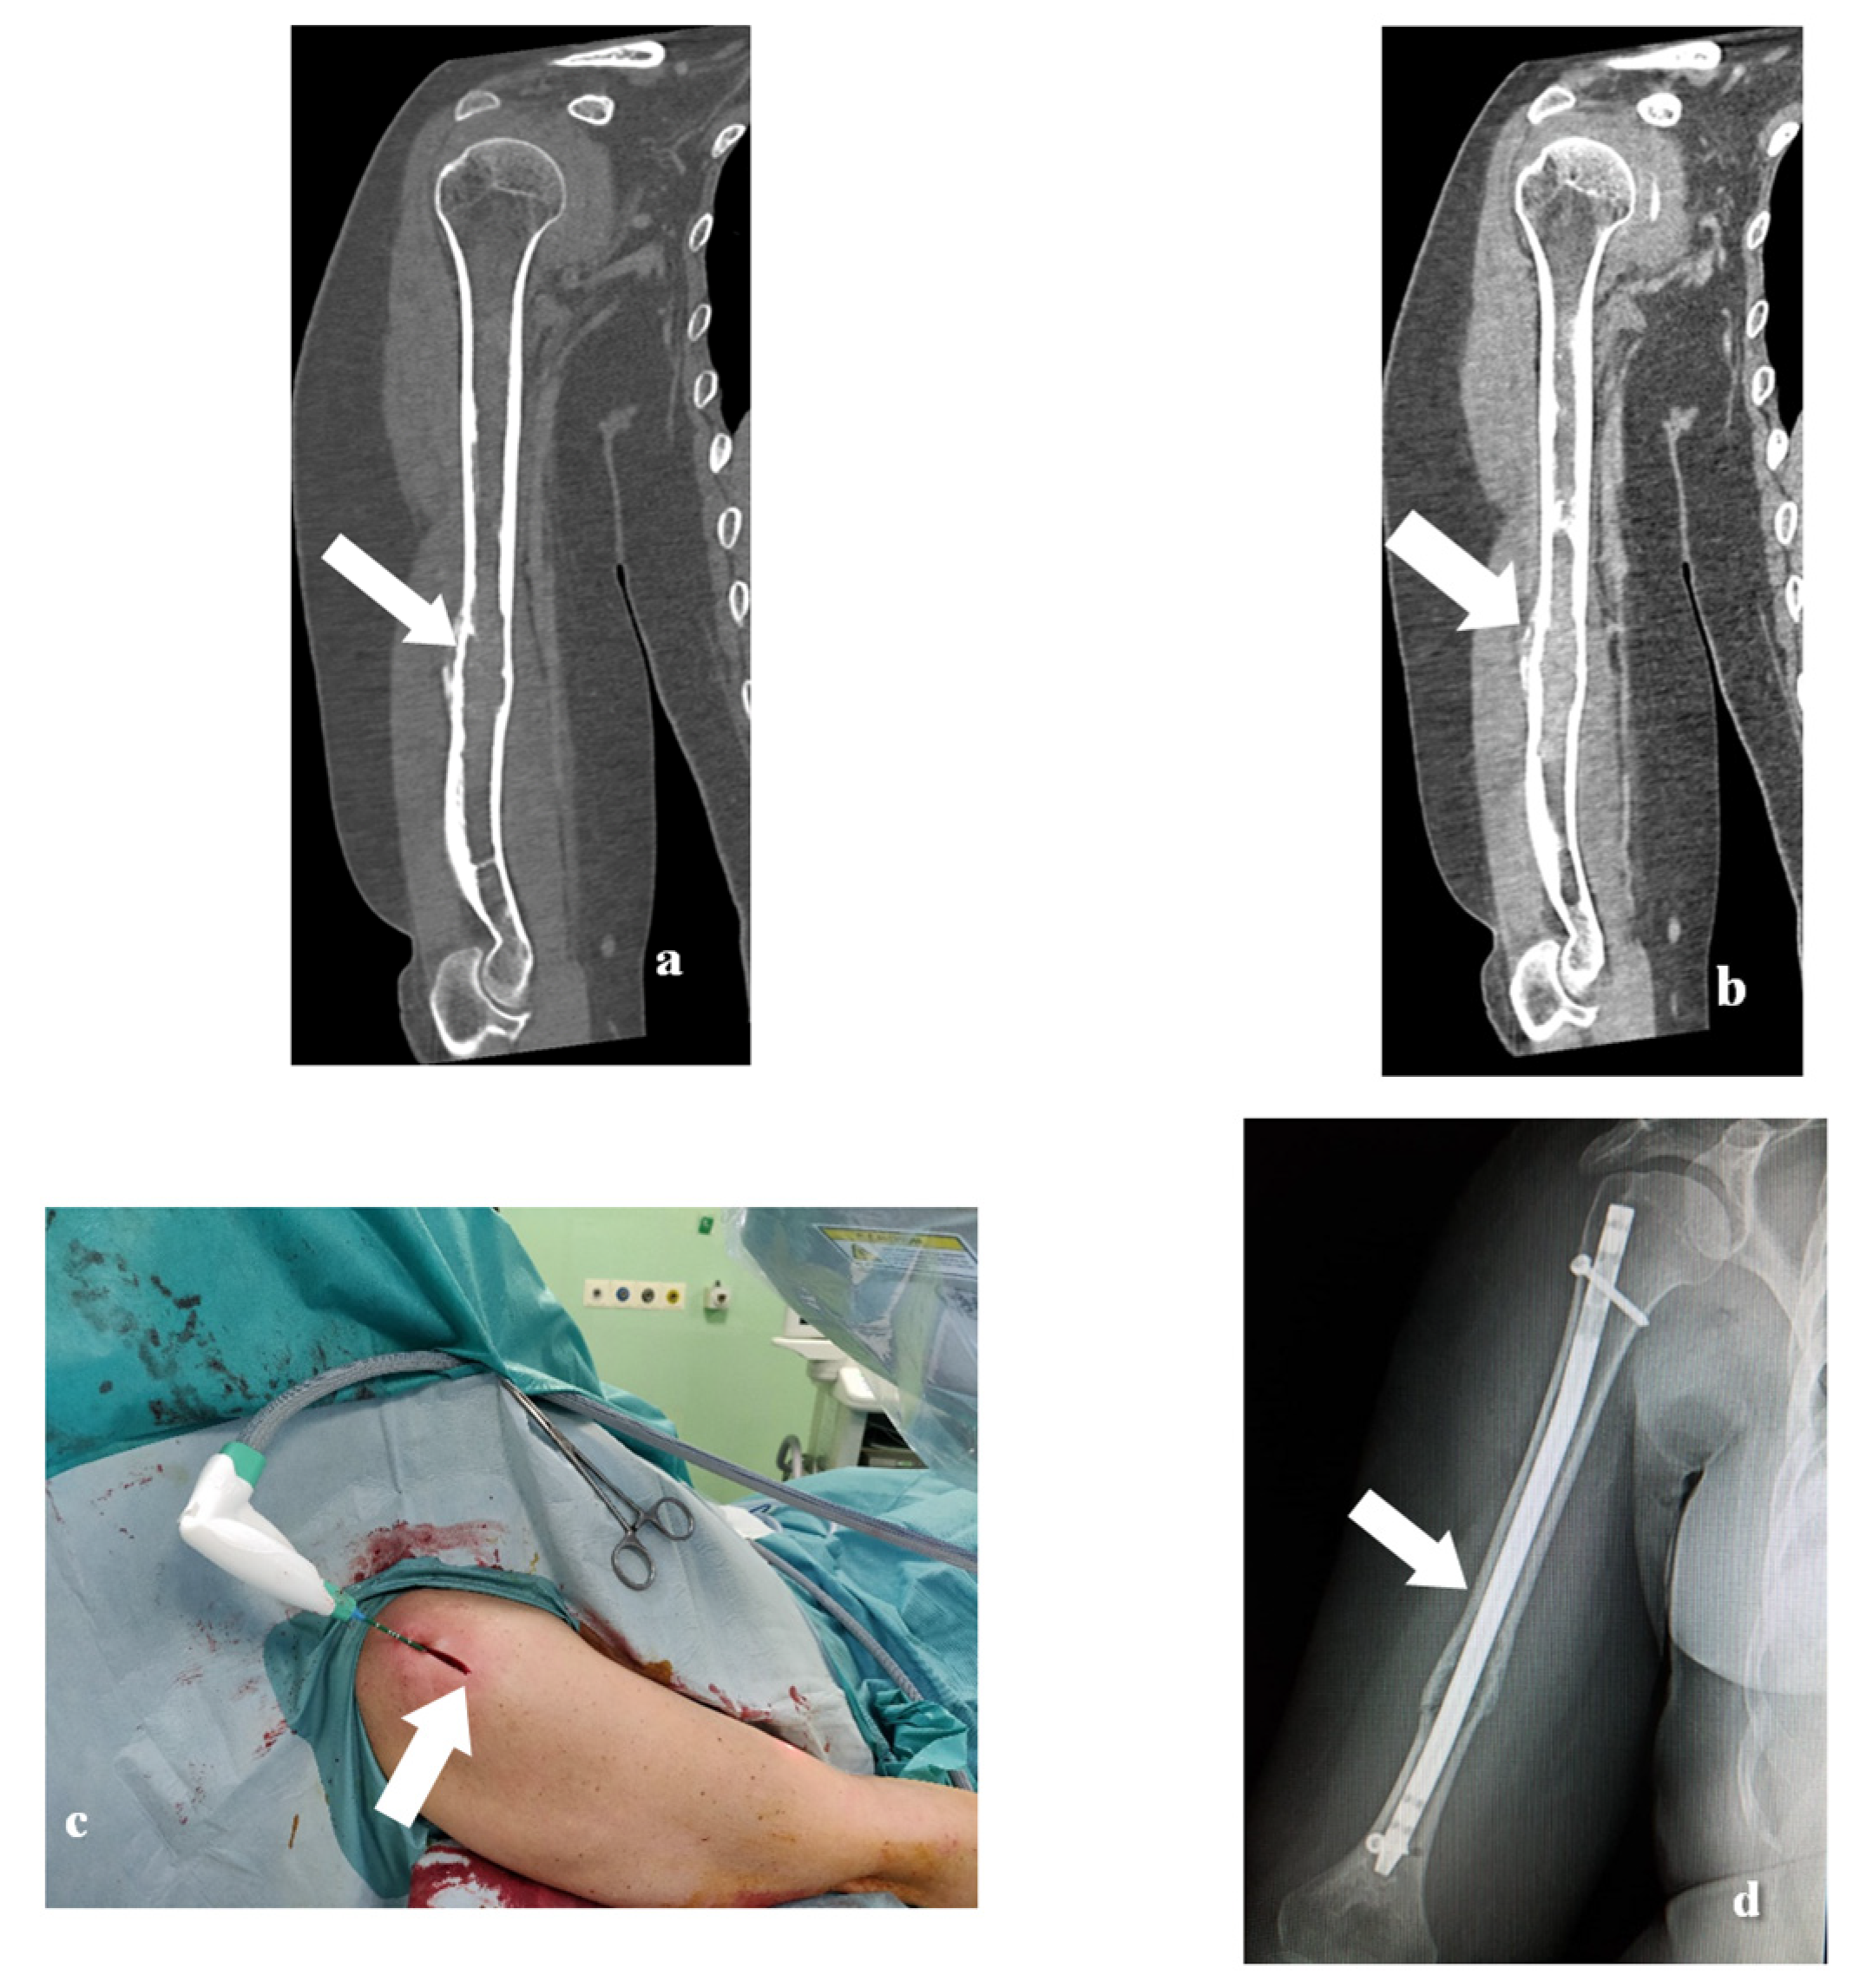

2. Materials and Methods

2.2. MWA Technique

2.3. Surgical Technique